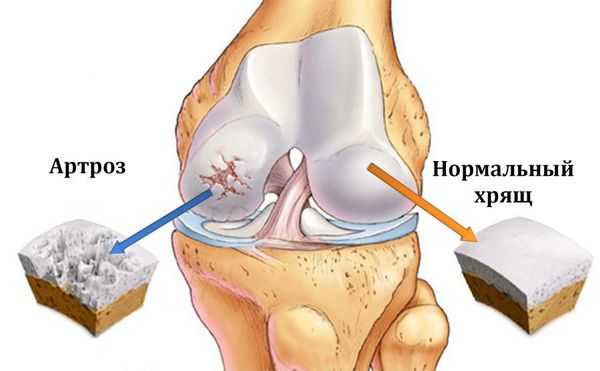

Деформирующий артроз - это хроническое заболевание хрящевой и костной тканей, которое связано с постепенным разрушением суставного хряща и утратой подвижности в сочленении. Из-за трения и микротравматизации головки вовлеченных костей начинают разрастаться и сплющиваться, что приводит к изменению внешнего вида сустава. Оставленный без лечения, деформирующий остеоартроз суставов может повлечь полную или частичную инвалидность больного с утратой способности заботиться о себе самостоятельно.

Эту стадию также называют стадией компенсации, поскольку организму удается компенсировать дефицит хрящевой ткани за счет возможностей опорно-двигательного аппарата. При деформирующем артрозе 1 степени изменения хрящевой структуры невелики и трудно диагностируются при помощи рентгенологического исследования.

Во время аппаратных исследований (рентген, УЗИ) заметно истончение хряща и уплотнение головок субхондральных костей. При этом в теле кости могут появляться кисты - полости, заполненные жидкостью, которые снижают прочность головки и могут стать причиной ее перелома. Питание хряща на 2 стадии болезни нарушено - чтобы восстановить его, требуется интенсивная терапия и высокая ответственность со стороны пациента. Для стадии субкомпенсации характерно появление остеофитов - костных наростов, которые нарушают здоровое сцепление и взаимодействие суставных поверхностей.

При деформирующем артрозе 3 степени наступает состояние декомпенсации. Синовиальный хрящ разрушен настолько, что обнажает костные головки полностью или частично. Сустав деформируется настолько, что это видно со стороны невооруженным глазом. Амплитуда движений в суставе сильно сокращается, появляются явные симптомы воспаления - локальное повышение температуры (кожа над сочленением становится горячей, чувствительной, краснее) и боль, которая беспокоит пациента почти постоянно.

На рентгене заметно критическое сужение суставной щели. Медикаментозная терапия на этом этапе уже неэффективна - улучшить ситуацию можно только хирургически.